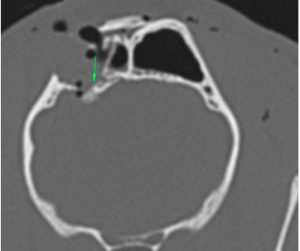

Milo was placed under general anaesthesia and an on-site CT scan of his head was performed.

This revealed that Milo had a comminuted fracture of the right frontal bone with a depression fragment compressing the right frontal lobe, associated with perilesional oedema and subdural haemorrhage.

He also had an incomplete fracture of his left frontal bone, a displaced fracture of the left zygomatic arch, as well as subcutaneous emphysema and hematoma of the soft tissue on the left side of his face.